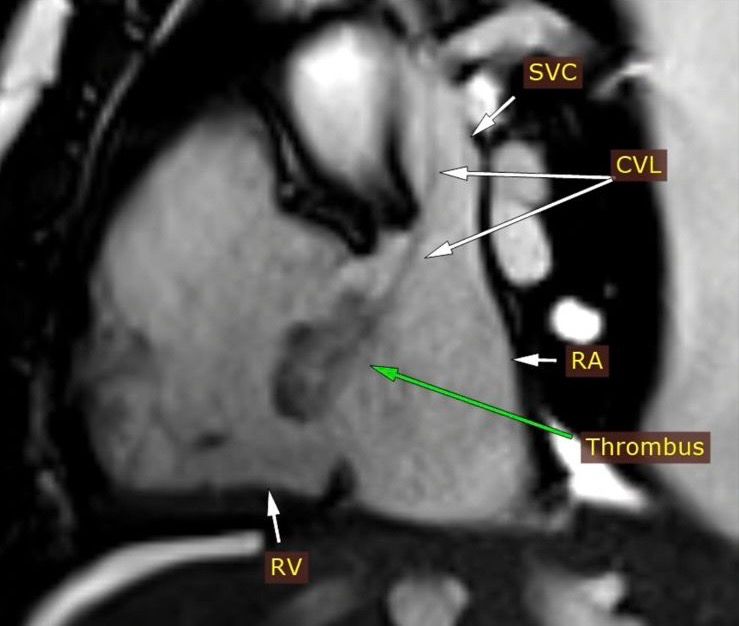

وأضاف الدكتور مجدي القاضي عميد كلية الطب البشري ورئيس مجلس اداره المسشفيات الجامعيه ان التقرير الطبي اوضح بعد إجراء فحوصات الإيكو للقلب، تبين اشتباه وجود ورم بالأذين الأيمن وعلى الفور تم تحويل المريض الى وحدة التصوير الطبى للقلب واجراء رنين مغناطيسى على القلب وتبين ان المريض يعانى من التهابات بعضلة القلب وتواجد جلطة بالاذين الايمن وتم تشخيص الحالة بدقة وتلقى العلاج المناسب بقسم امراض القلب والاوعيه الدمويه.

وأشار الدكتور عمرو الشريف، نائب مدير المستشفى ومدير الوحدة، أن الوحدة مزودة بأحدث الأجهزة الطبية، وتشمل جهازي أشعة مقطعية متعددة المقاطع من نوع GE 128 Slice وCannon 160 Slice، بالإضافة إلى جهاز رنين مغناطيسي 1.5 تسلا، وتقوم بإجراء جميع فحوصات القلب المتقدمة، منها الأشعة المقطعية للشرايين التاجية، والمقطعية لتشخيص العيوب الخِلقية بالقلب، وأشعة الرنين لتشخيص تأثير الجلطات على عضلة القلب وأمراضها المختلفة.